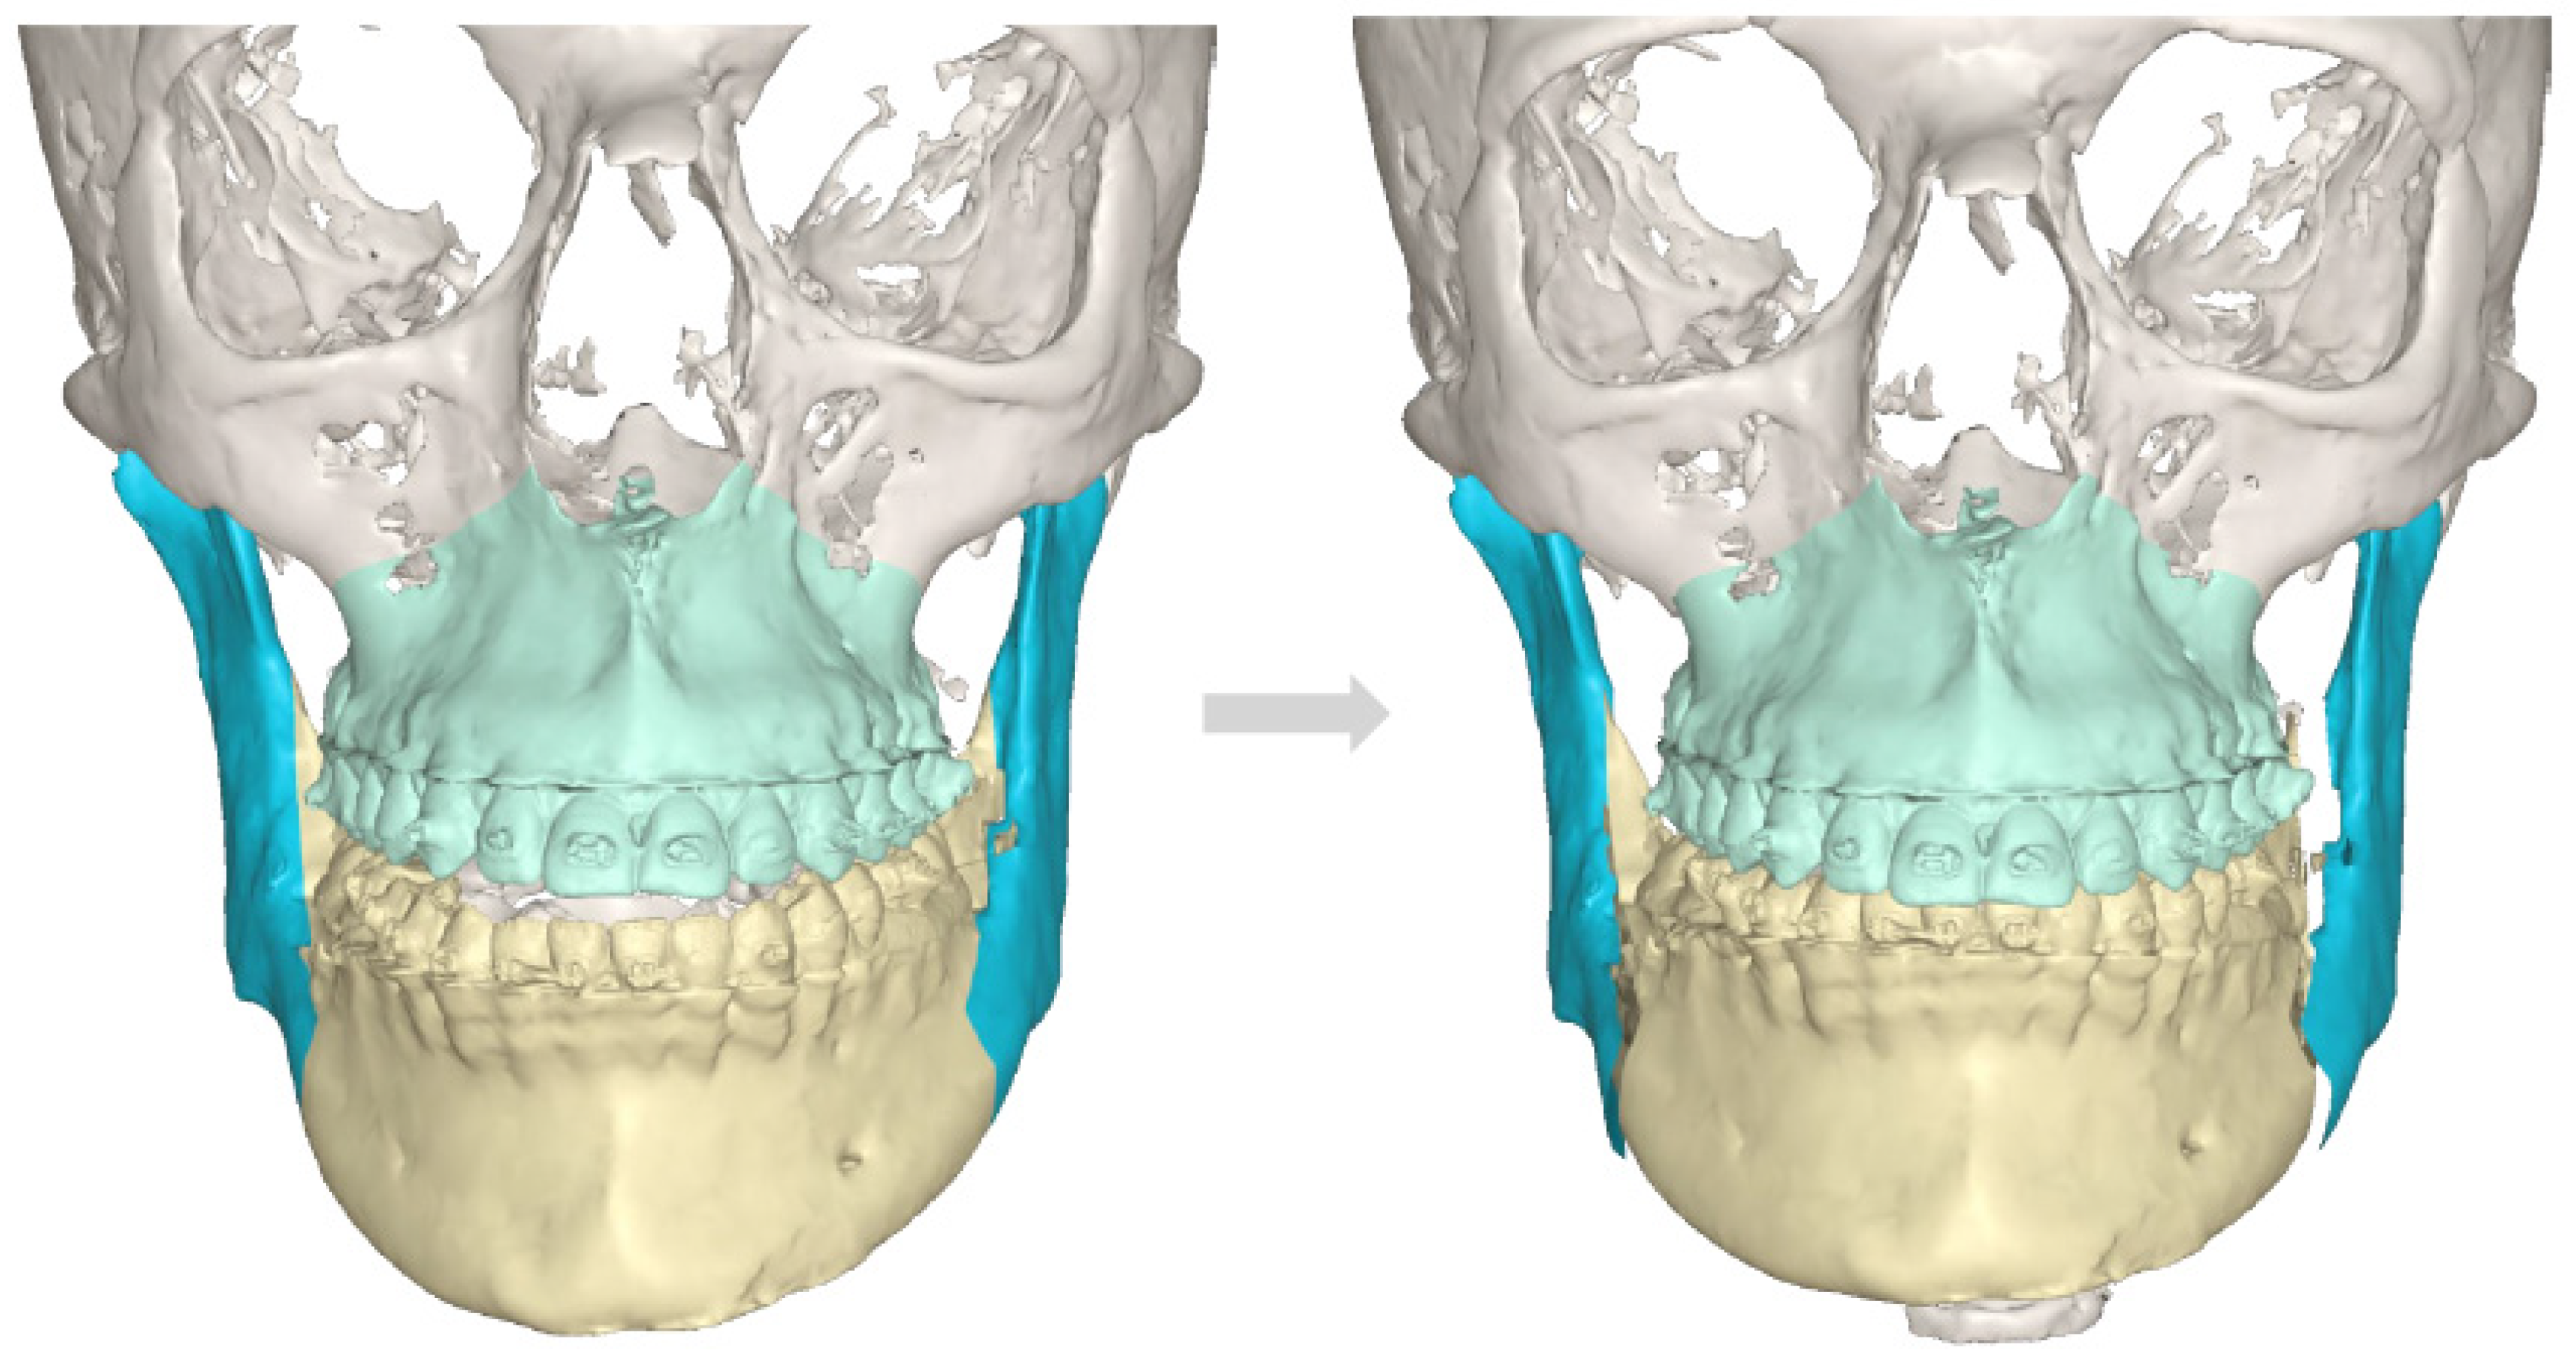

Figure 5.

A CBCT-3D reconstruction with visible enlargement and overgrowth of the left mandibular condyle head. Also, a tendency for skeletal class III deformity is visible. In such cases of severe skeletal asymmetries, a necessity for orthognathic surgery procedures is quite important to improve facial symmetry, oval, and contour. The presented images are quite interesting because the unilateral condylar hyperplasia in this case slowly grew over the years and was not found before the first orthognathic procedure in the past; this was the main source of skeletal asymmetry relapse over the next years.